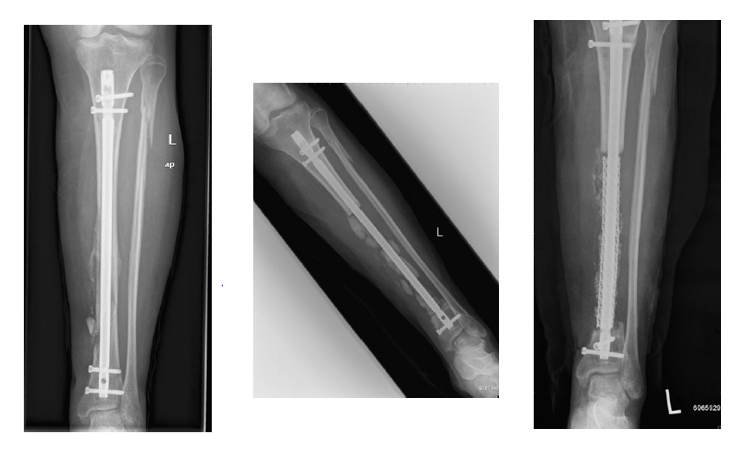

技术改进Stage I   直接使用内固定

长节段骨缺损使用Cage作为局部植骨支架

17cm骨缺损